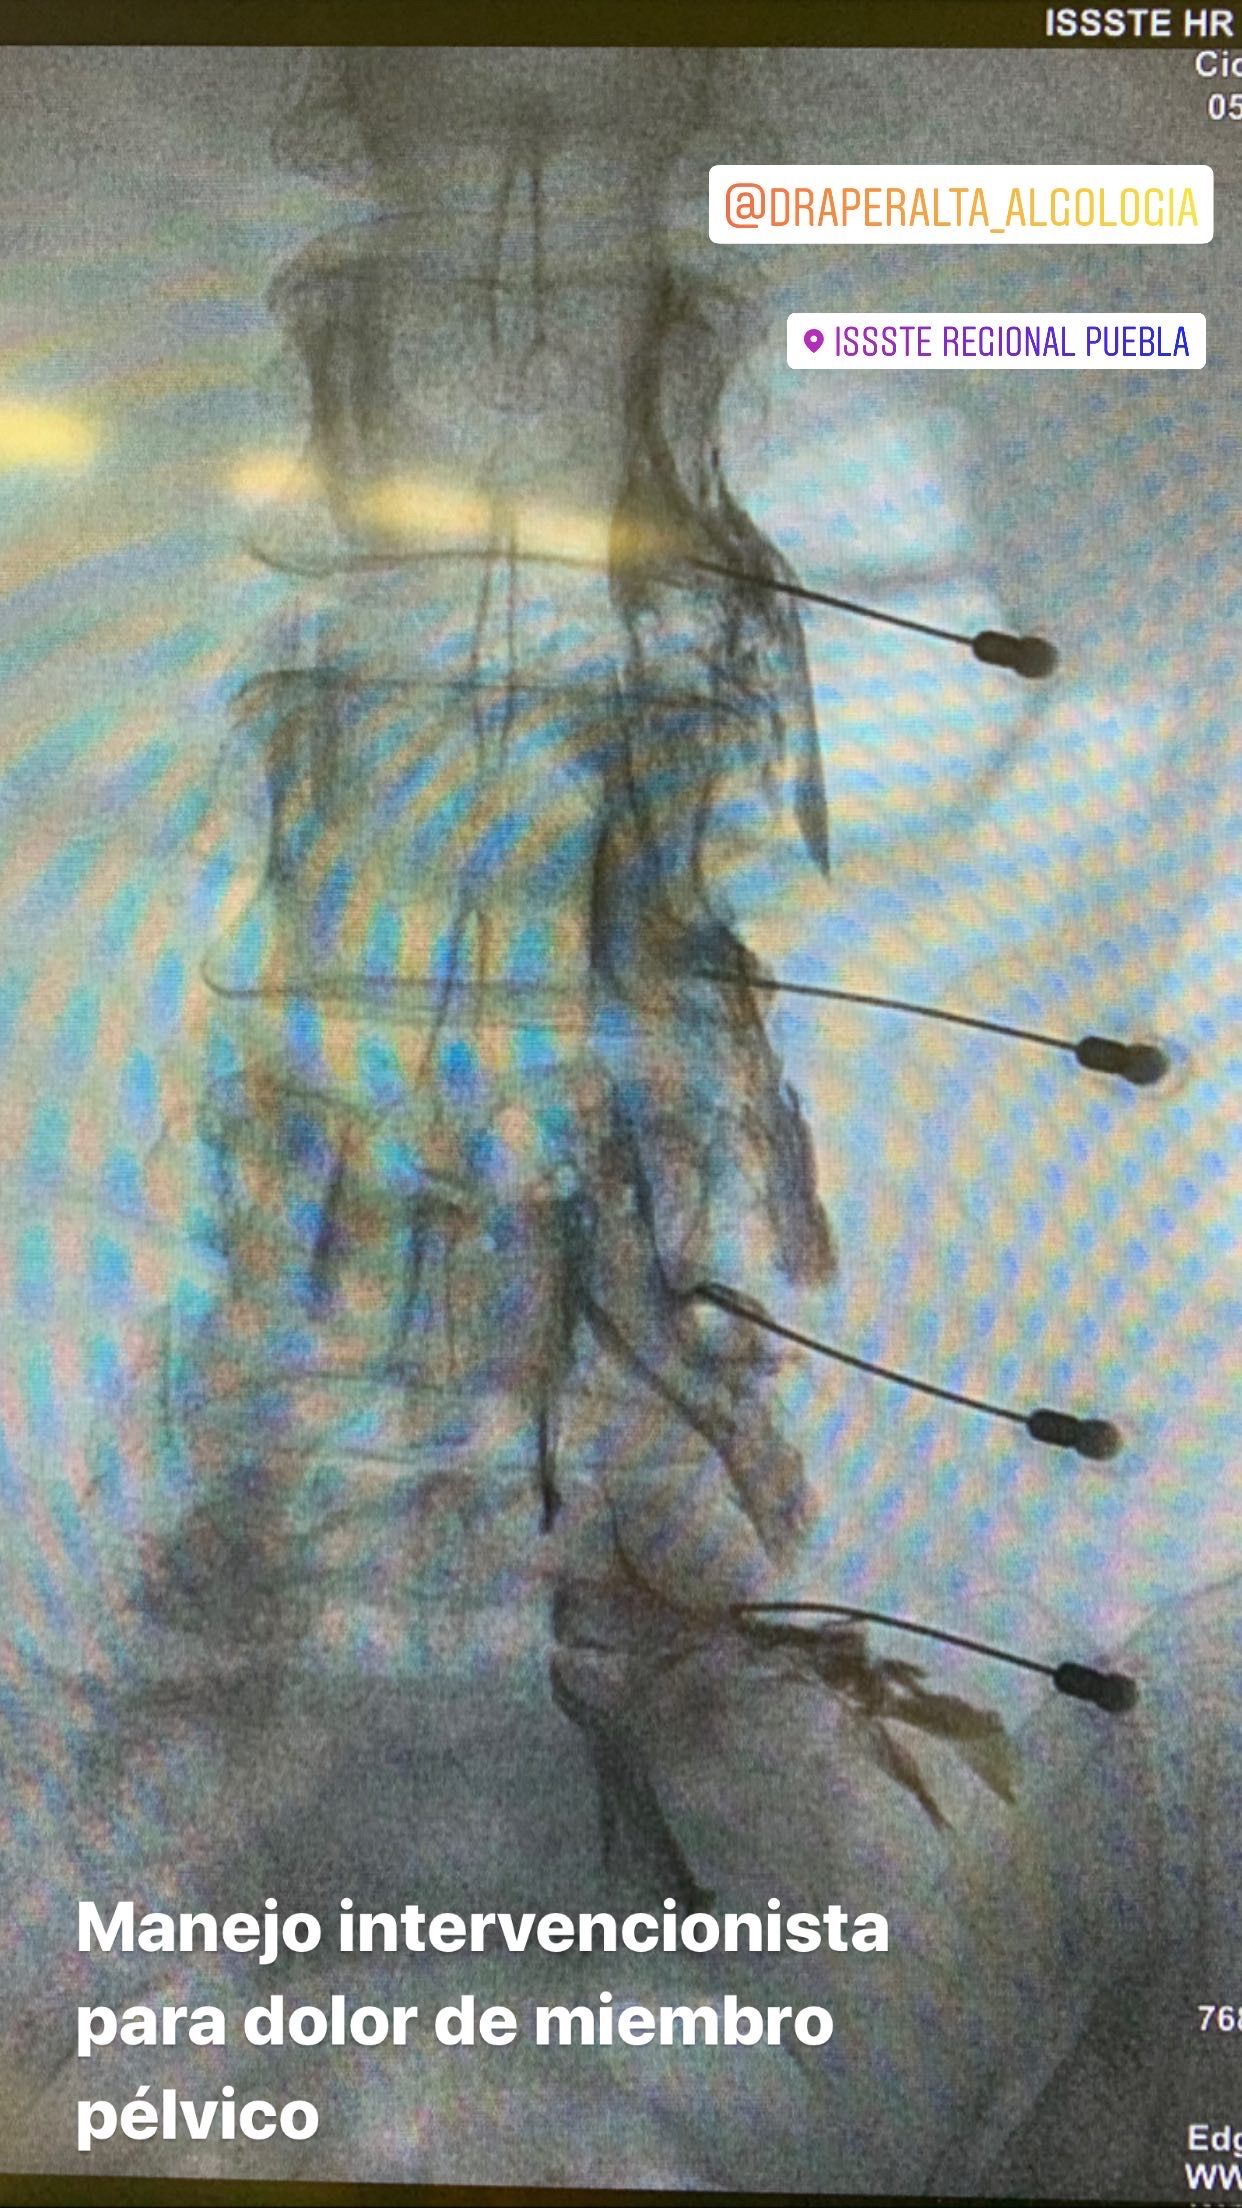

-Manejo intervencionistas para disminuir el consumo de medicamentos:

9.- Colocación de neuroestimulador de cordones posteriores.